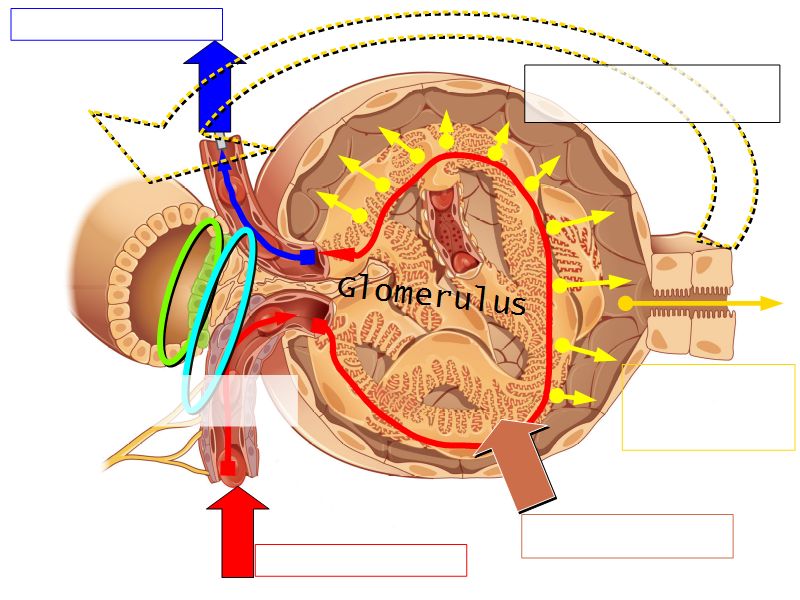

Renal corpuscle

- Tuft of capillaries

- grow into

- Blind end of nephron

- Several layers of epithelium

- Two sides

- Vascular pole

- Tubular pole

Blood flow

- Efferent arteriole

- Smooth muscle in media

- Capillaries

- Fenestrated

- Afferent arteriole

- Smooth muscle in media

Epithelium layers

- Capillary endothelium

- Visceral layer of epithelium

- Podocytes

- Resting on glomerular basement membrane

- Capsular space

- Parietal layer of epithelium

- Simple squamous epithelium

Glomerular filtration barrier

- Three layers

- Fenestrated epithelium

- Exclude blood cells & platelets

- Glomerular basement membrane

- Main filtration barrier

- Thick

- Fused epithelial & endothelial BM

- Replenished by podocytes due to removal by mesangial cells

- Glomerular epithelium

- Through filtration slit

Juxtaglomerular complex

Area where distal convoluted tubule return to glomerulus and pass through the notch between the afferent and efferent arterioles. Modification of the wall of the tubule and afferent arteriole and presence of specialised cells in the connective tissue.Modifications